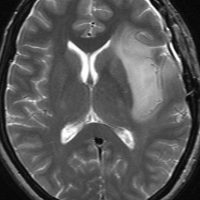

expanding, solid 固形腫瘍的なもの

壊死ではない「のう胞」を伴い,ガドリニウムで強く増強されます。グレード 4 (膠芽腫)と間違えるようなものです。しかし,のう胞はありますが中心壊死がありません。

腫瘍を大部分摘出できるので,積極的な摘出術をして,手術後には放射線化学療法を加えます。この例では,手術後の放射線治療計画の領域が狭ければ,60グレイを使用できる部位です。